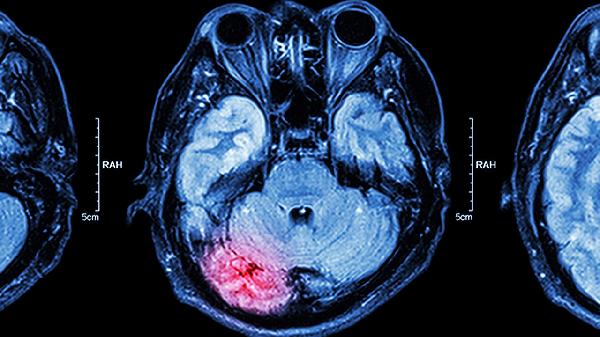

激光间质热疗是新兴的微创治疗手段,将激光光纤导入肿瘤内部产生高温消融。适用于复发性胶质瘤或转移瘤,能保护周围正常脑组织。治疗后可出现暂时性神经功能缺损,需配合甘露醇注射液减轻脑水肿。

术后需保持伤口清洁干燥,避免剧烈运动或头部碰撞。饮食应选择高蛋白食物如鱼肉、鸡蛋帮助组织修复,适量补充核桃、深海鱼等富含欧米伽3脂肪酸的食物促进神经恢复。定期进行认知训练和肢体康复锻炼,按医嘱复查头颅CT或MRI监测肿瘤变化。出现持续头痛、呕吐或意识改变时需立即就医。